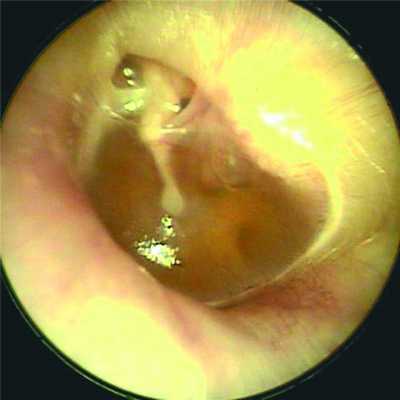

Аттиковые ретракции были неглубокие, с отоскопически контролируемым дном (рис. 2 на цв. вклейке). Рисунок 2. Аттиковая ретракция II типа (с контролируемым дном). Вязкий экссудат в барабанной полости (стадия сукозита). Только в 2 (7,4%) случаях/3 (7,0%) уха дно кармана не визуализировалось.